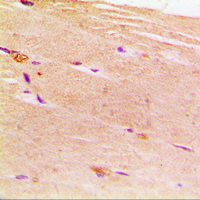

- Experimental details

- Immunohistochemical analysis of ACTN2 staining in human muscle formalin fixed paraffin embedded tissue section. The section was pre-treated using heat mediated antigen retrieval with sodium citrate buffer (pH 6.0). The section was then incubated with the antibody at room temperature and detected using an HRP conjugated compact polymer system. DAB was used as the chromogen. The section was then counterstained with hematoxylin and mounted with DPX.